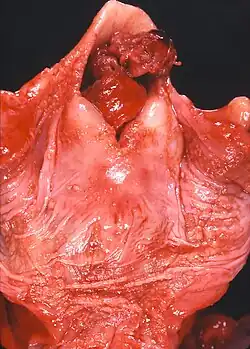

.jpg)